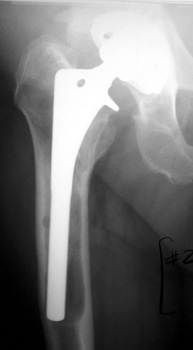

COMPONENT MIGRATION

SUBSIDENCE

SUBSIDENCE - loose femoral prosthesis with interface widening,

osteolysis Gruen zone 6, cement fracture left femoral component

and osteolysis, with femoral component in valgus.